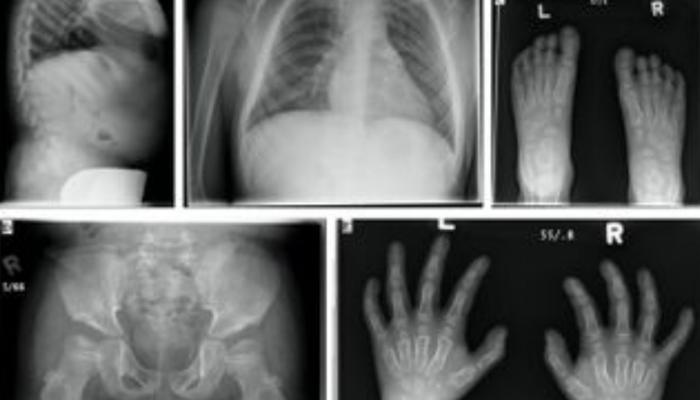

بیماری موركیو از جمله اختلالات ذخیرهای لیسوزومی است که بر اثر کمبود آنزیم «N-استیل گالاکتوزامین-6-سولفات» رخ میدهد. این آنزیم مسئول تجزیه نوعی از قندهای پیچیده موسوم به کراتین و همچنین ترکیبات سلفات است. نبود یا کاهش شدید فعالیت آنزیم باعث انباشت این مواد در بافتهای مختلف بدن میشود؛ موضوعی که به بروز مجموعهای از مشکلات جسمی از جمله ناهنجاریهای اسکلتی، اختلالات قلبی، تغییر رنگ قرنیه و مشکلات مفصلی منجر میشود. با این حال عملکرد ذهنی بیماران معمولاً طبیعی باقی میماند.

بر اساس نسخهای از این پژوهش که در اختیار «العین نیوز» قرار گرفته و قرار است در شماره جدید نشریه «ژنتیک مولکولی و متابولیسم» منتشر شود، وضعیت ۳۳ کودک از ۲۶ خانواده متفاوت مورد بررسی قرار گرفته است. دادهها نشان میدهد بیش از ۹۰٪ از این کودکان حاصل ازدواجهای خویشاوندی بودهاند؛ موضوعی که بار دیگر نقش ازدواجهای فامیلی را در افزایش خطر ابتلا به بیماریهای ژنتیکی نادر پررنگ میکند. اغلب این کودکان با تأخیر رشد، ناهنجاریهای شدید استخوانی، تغییر رنگ قرنیه، اختلالات دریچه قلب و درجاتی از افت شنوایی روبهرو بودند.